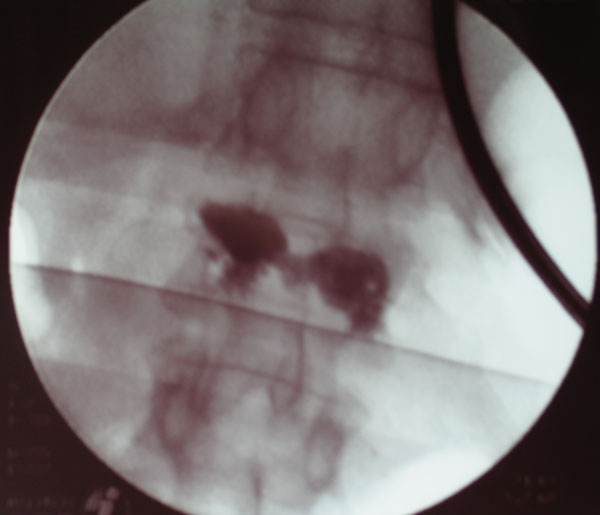

Bei der Kyphoplastie handelt es sich um eine Variante der Vertebroplastie. Genau wie bei der konventionellen Vertebroplastie werden unter Computertomographischer bzw. Röntgenbildwandlerkontrolle ohne Hautschnitt über einen minimalinvasiven Zugang zwei Kanülen transpedikulär (durch die Wirbelbogenwurzel, s.o.) eingebracht. Über die Kanülen werden zwei Arbeitskanülen eingebracht, über diese werden wiederum zwei mit Röntgenkontrastmittel „aufblasbare“ Ballons in den gebrochenen Wirbel eingeführt. Diese Ballons werden nunmehr unter Röntgenkontrolle und elektronischer Druckkontrolle vorsichtig aufgeblasen. Hierunter kommt es idealerweise zu einer nahezu vollständigen Wiederherstellung der ursprünglichen Wirblkörperkontur. Hiernach wird das Kontrastmittel aus den Ballons abgelassen, die zusammengefallenen Ballons können über die Arbeitskanüle entfernt werden. In den nunmehr im gebrochenen Wirbel gewonnenen Hohlraum wird dann über weitere spezielle Kanülen der vorbereitete Knochenzement ohne Druck eingespritzt.